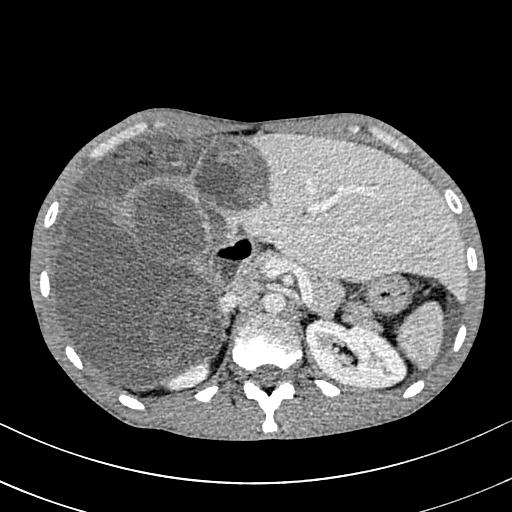

Une tomodensitométrie abdomino-pelvienne est réalisée sans et après injection de produit de contraste. Cette dernière, montre au niveau du foie droit Corresponding Author ?: Internat Hôpital Ibn Sina 40010 Rabat, Maroc. e-mail: [email protected] de multiples formations kystiques, à contenu liquidien pur ou cloisonné, bien circonscrites, confluentes, à paroi épaissie rehaussées en périphérie après injection de produit de contraste en rapport avec des kystes hydatiques hépatiques de taille et de type variable.

Il s'y associe également au niveau pelvien deux kystes hydatiques intra-péritonéaux, le premier est multi vésiculaire et le deuxième sus et latéro-vésicale gauche à paroi affaissée, discontinue associée à un épanchement péritonéal témoignant sa rupture dans la cavité péritonéale.

Le diagnostic de péritonite aigue généralisée par rupture d'un kyste hydatique intra-péritonéal associée à une hydatidose hépatique est retenu.